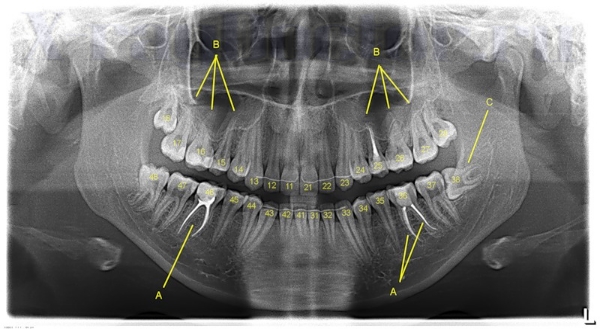

Ортопантомография (ОПТГ)

ортопантомографияПрименяется в стоматологии, практике ЛОР-заболеваний, хирургии челюстно-лицевого отдела черепа, а также в косметологии. Как и во всех диагностических методах, использующих рентген, в ортопантомографии наблюдается тенденция перехода с пленочного варианта на цифровой формат.

ОПТГ способствует установке и уточнению диагноза, помогает контролировать ход лечения.

Рентгенологические методы диагностики активно используются в стоматологии. Без рентгена сложно себе представить стоматологическое лечение высокой и средней степени сложности. Патологии костей черепа и воспалительные процессы мягких тканей также являются показанием для назначения данного способа диагностики.